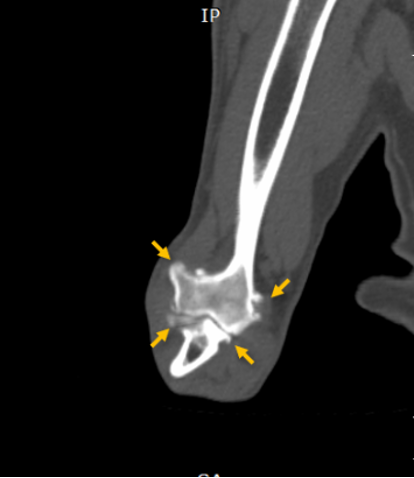

영상 검사 – CT로 확인된 원인

초기 엑스레이 검사에서는 뚜렷한 이상이 확인되지 않았습니다. 하지만 FMCP는 작은 뼛조각이 원인이 되는 질환이기 때문에, 보다 정밀한 검사가 필요하다고 판단되어 CT 촬영을 진행하였고, 그 결과 척골 내측 구상돌기의 분리된 뼛조각이 명확하게 확인되었습니다.

대형견 강아지 FMCP CT 촬영 / 출처: 에스동물메디컬센터

최종적으로 대형견 강아지는 다음과 같은 최종 진단을 받게 되었습니다.

📌 대형견 강아지 앞다리 절뚝거림 최종 진단

✔️ 내측 구상돌기 분리증(FMCP)

✔️ 이차적인 퇴행성 관절염(Degenerative Joint Disease)

특히 이미 연골 손상이 일부 진행된 상태로 판단되어, 빠른 치료가 필요한 상황이었습니다.